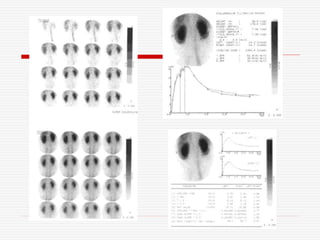

Left kidney

Right kidney

75 year-old lady

– OIH study